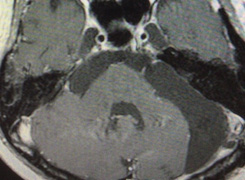

手術後